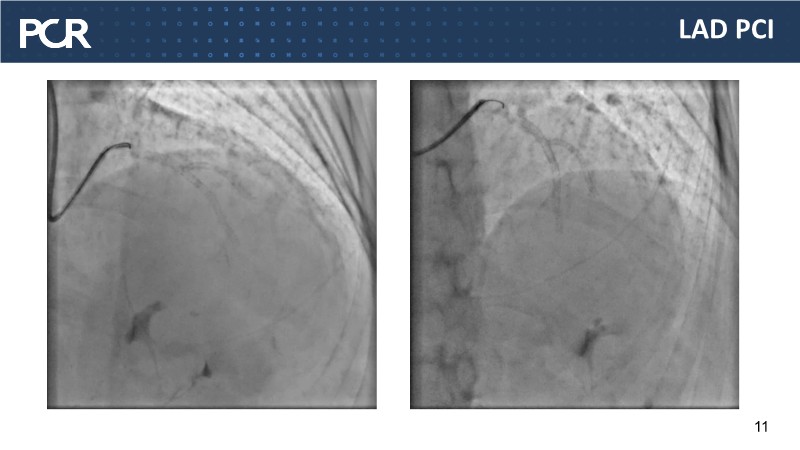

This EuroPCR 2025 session highlights how CathWorks FFRangio is reshaping coronary physiology assessment worldwide. Through case-based experience and real-world data, it showcases the integration of FFRangio into routine clinical workflows—from early adoption at Clinique Pasteur in Toulouse to implementation across the UK. The session also presents the growing body of diagnostic and clinical outcome evidence, along with a look at how FFRangio is evolving toward becoming a new standard of care in the cathlab.

- To explore the practical application of FFRangio in routine practice